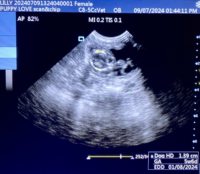

Mobile Ultrasound Pregnancy Scanning and Microchipping Services

Puppy Love scan and chip